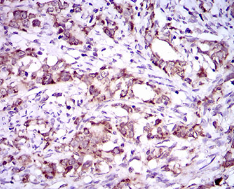

| AC2092 | DNAL4 Mouse Monoclonal antibody[3C24] | 100ug | $367 | 10days |

| AC2092 | DNAL4 Mouse Monoclonal antibody[3C24] | 200ug | $660.6 | 10days |